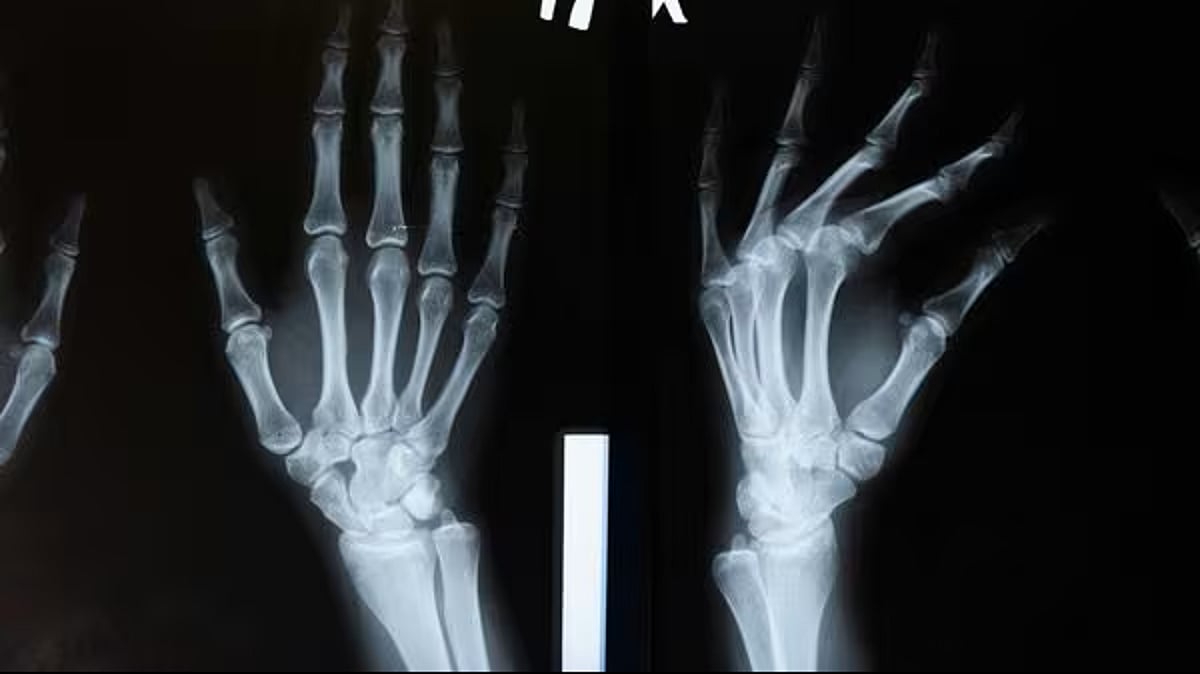

أعلن فريق بحثي في مقاطعة تشيجيانغ شرق الصين، تطوير “غراء عظمي” جديد باسم Bone-02، قادر على تثبيت الشظايا العظمية المكسورة خلال ثلاث دقائق فقط، في خطوة وُصفت بأنها “اختراق علمي” في جراحة العظام.